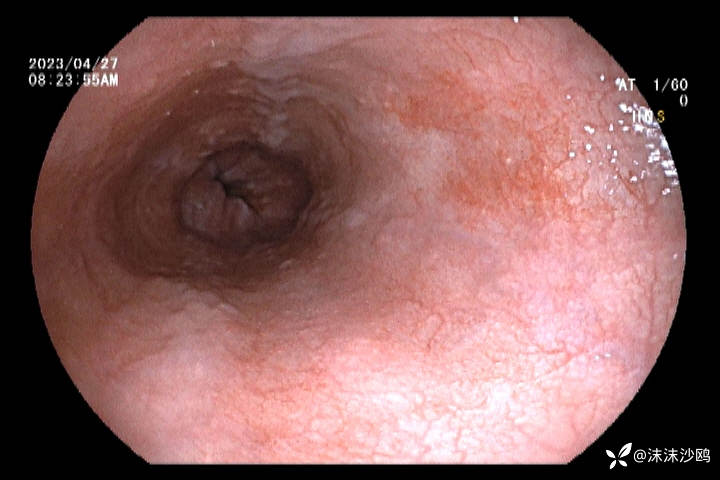

23年4月份

今天的,做了放大,但我们没有碘染色剂,所有没做碘染。

后三次都是我做的,因为今天对比了病灶,感觉变化不明显,没有取病检。